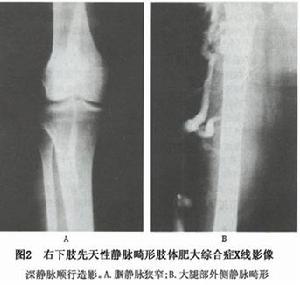

3.靜脈造影檢查靜脈造影檢查包括:①深靜脈順行造影:可見靜脈走行異常、狹窄、閉塞,或主幹靜脈部分缺如;靜脈瓣膜形態異常,功能不全,或瓣膜缺如;淺靜脈迂曲、擴張有瘤樣變,深淺靜脈交通支瓣膜功能不全,血液倒流(圖2);②深靜脈逆行造影:可了解深靜脈因瓣膜功能不全所引起的血液倒流的程度;③經皮膕靜脈插管造影:凡順行造影顯示膕靜脈通暢者,即可採用本檢查方法,既可明確瓣膜功能不全所引起的血液倒流的範圍和程度,又能對順行造影時髂-股靜脈段顯影不清者,進一步判別有無病變存在或病變的情況;④經曲張淺靜脈造影:可明確外側畸形靜脈注入深靜脈的途徑和部位。